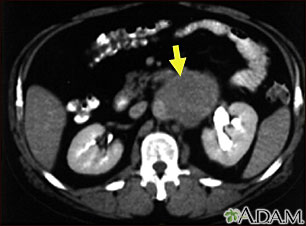

The abdominal CT scan may reveal the following kidney problems:

- Blockage of the kidneys

- Hydronephrosis (kidney swelling from the backflow of urine)

- Kidney infection

- Kidney stones

- Kidney or ureter damage

- Polycystic kidney disease

Abnormal results may also be due to:

- Abdominal aortic aneurysm

- Abscesses

- Appendicitis

- Bowel wall thickening

- Crohn disease

- Renal artery stenosis

- Renal vein thrombosis